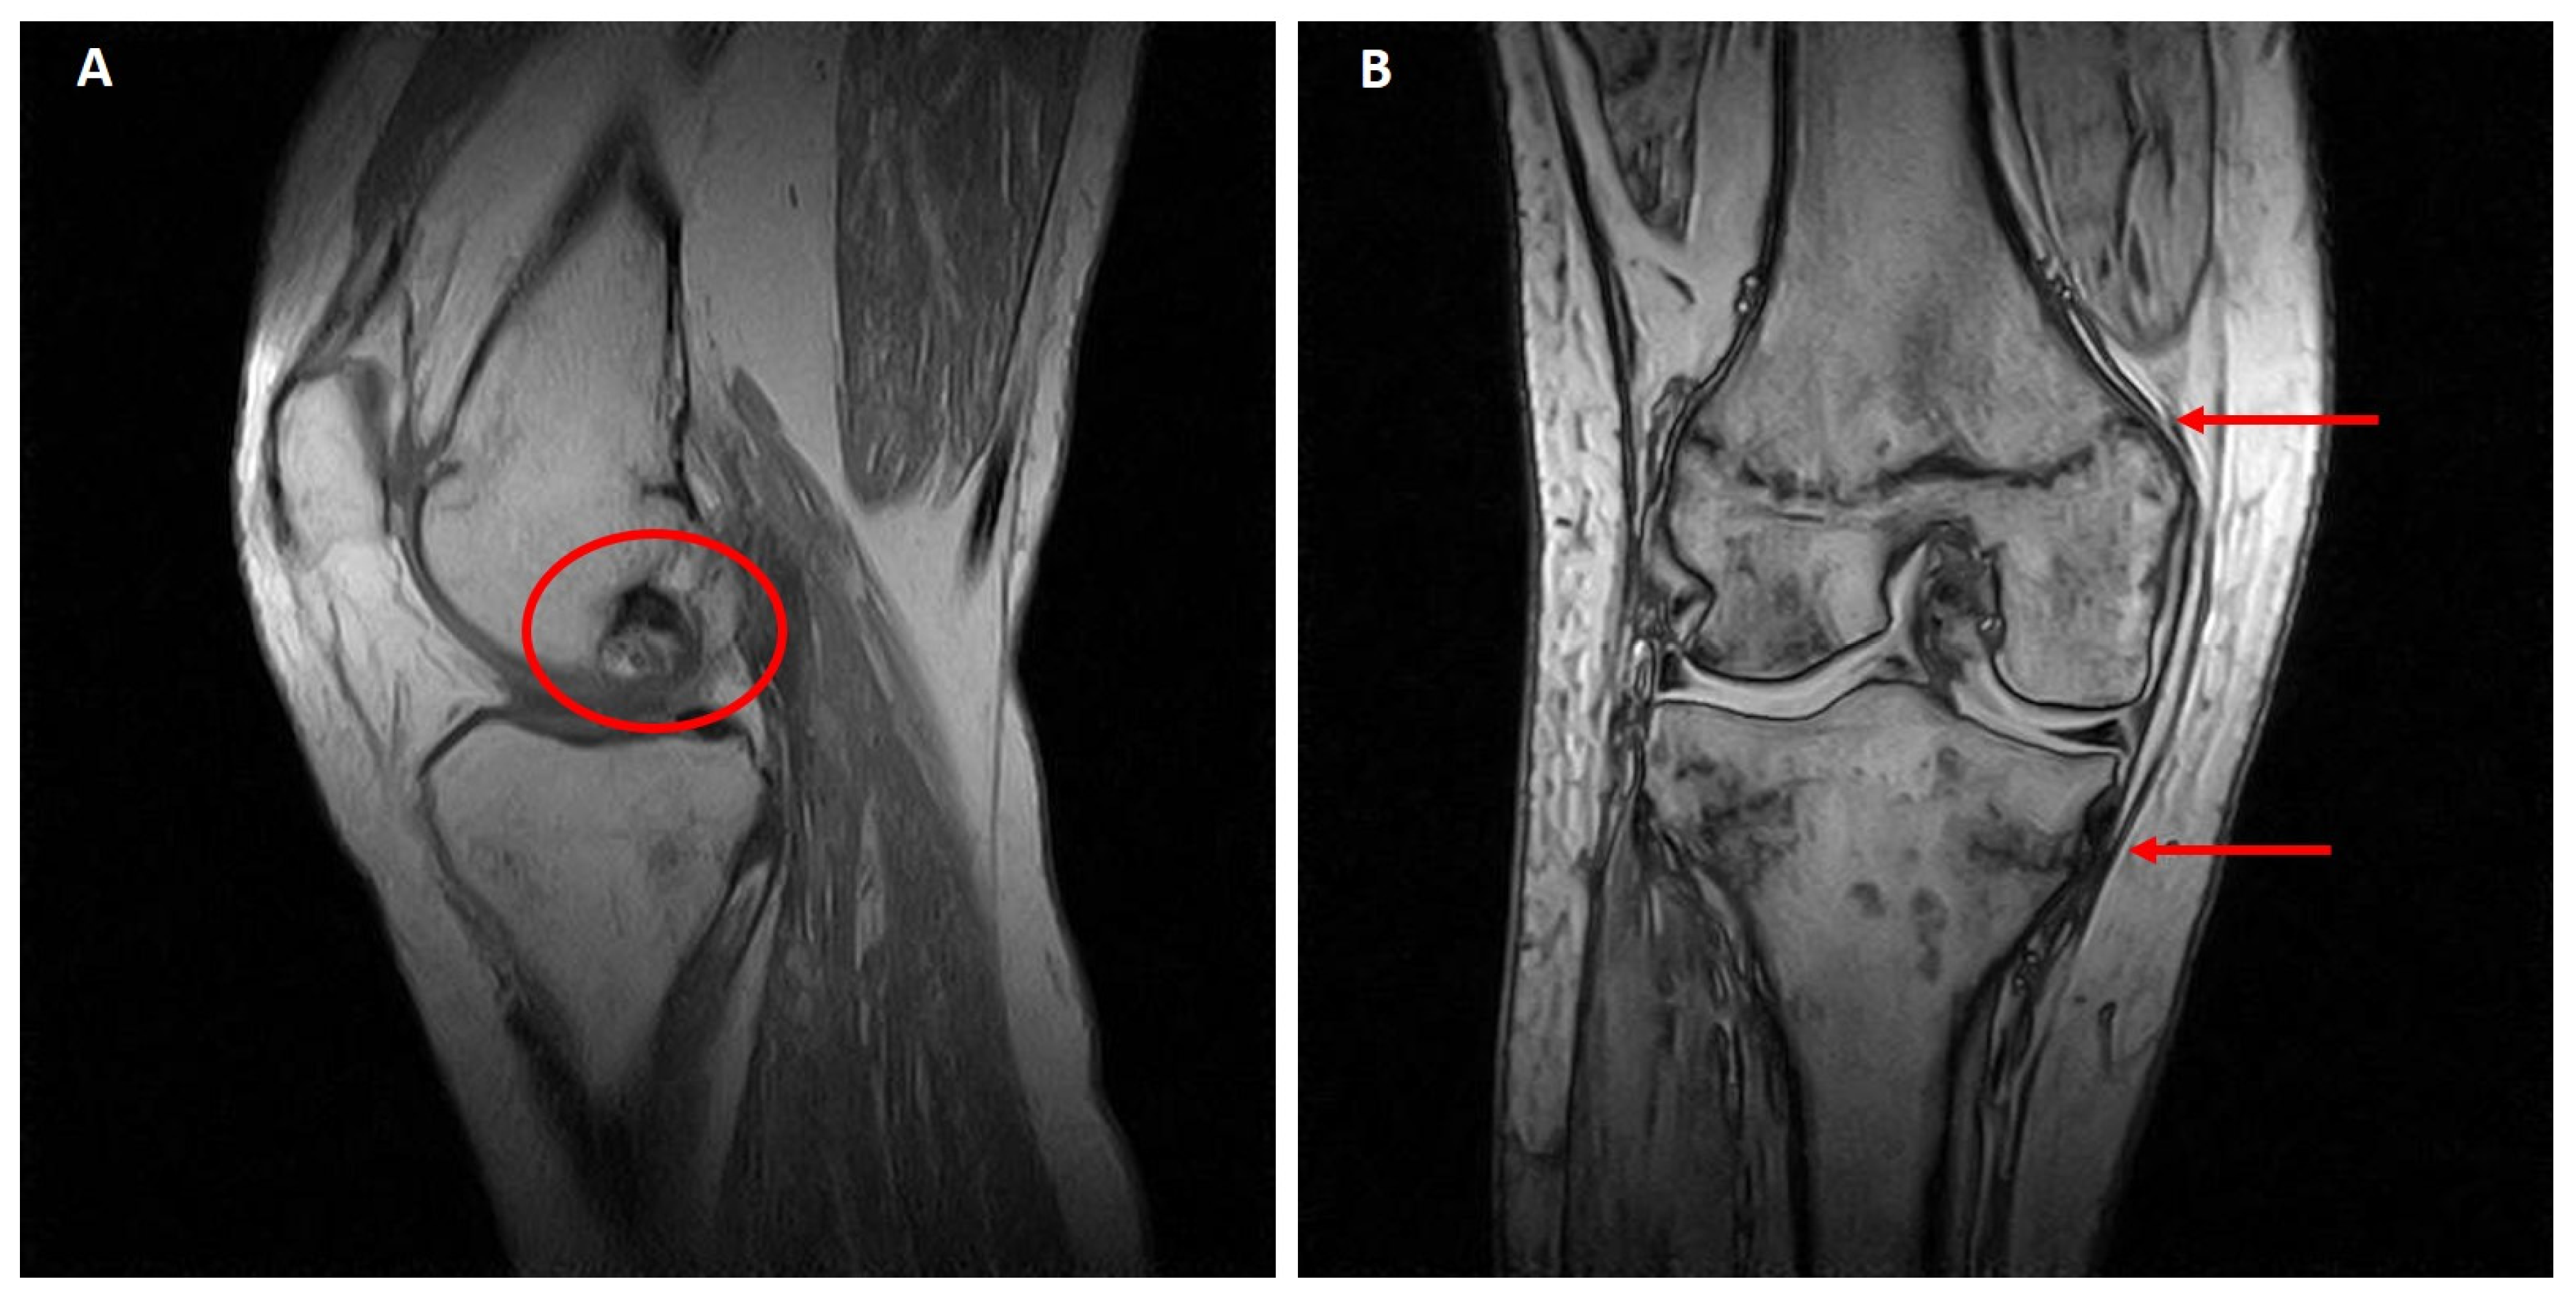

Figure 4. Global PET (Ga68-DOTATOC). (A) Spine. The white arrow indicates hypercaptation at T12/L1. (B) Skull. The white arrow indicates a focal area of increased uptake (max. axial diameter 13 mm).

Although the DEXA cannot be considered a radiological examination/imaging diagnostic tool, the left femoral neck appeared much shorter, compatible with a closed fracture. Moreover, and more interestingly, at the T12/L1 spine level, an hyperdense area was clearly detectable. This was further investigated by the mean of Global PET Ga68, that showed hypercaptation at the expansive formation in T12-L1 with narrowing of the vertebral canal and bone lysis at the L1 vertebral body and transverse and spinous processes levels. Moreover, the exam denoted an increased uptake in a small encephalic area of the frontal cortex (Figure 4A,B).